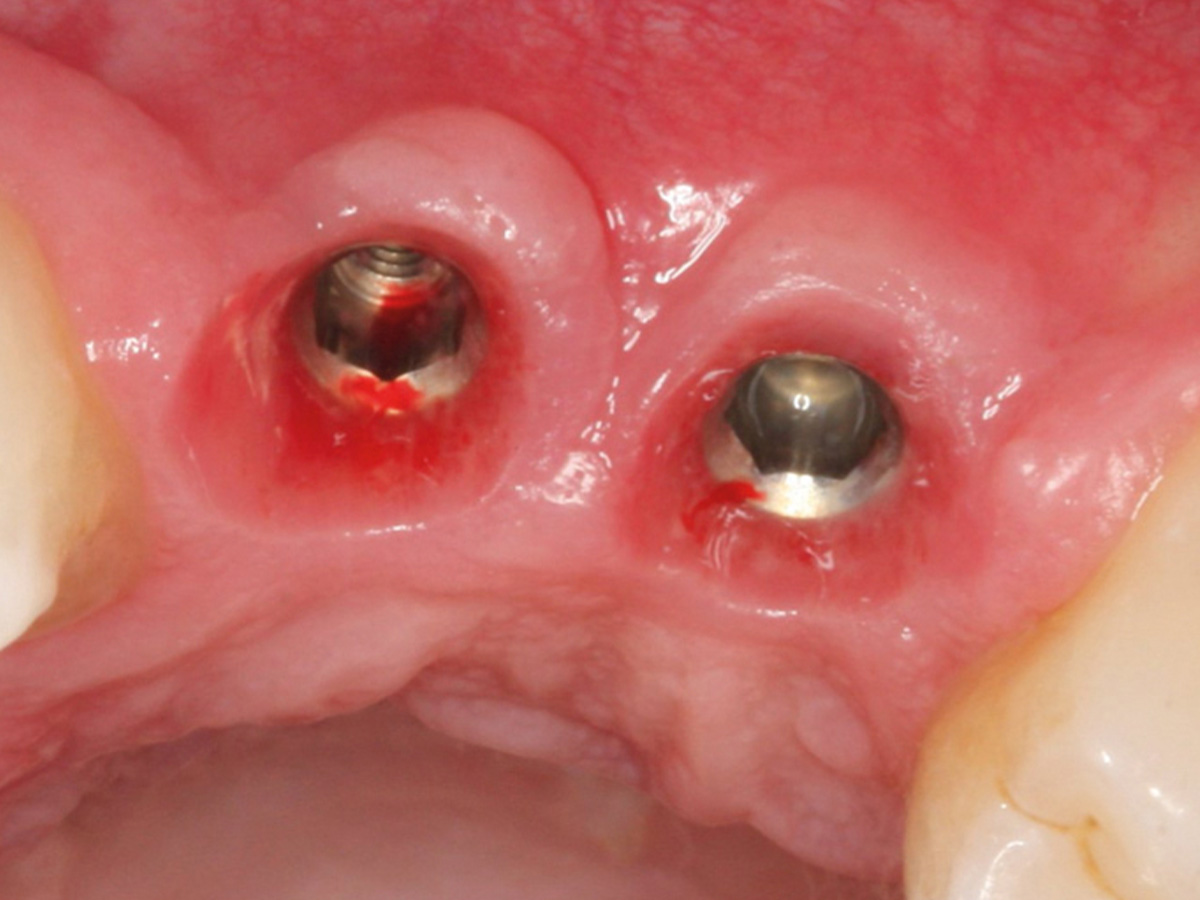

Abbildung 22

Darstellung der Implantat-Kavitäten im neuen Knochen.